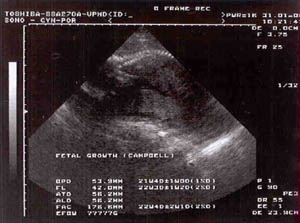

Bohužel jsem neviděla na monitor, to bylo prozatím dopřáno jen Skokymu. Pan doktor kontroloval všechny vnitřní orgány a co viděl, hlásil sestřičce, která zapisovala do těhotenské průkazky. Všechno snad vypadá být v pořádku, o ničem špatném nás doktor neinformoval. Sestřičce hlásil: "1 plod, akce +, plodové vody dostatek, pak nějaké zkratky a čísla, které jsou zapsány, ale ve kterých se nevyznám (BPP, ABD, f). Hlava, obličej, páteř, břišní stěna, odstup pupečníku, srdce 4 oddíly, křížení cév normální, žaludek naplněný +, ledviny +, močový měchýř +, končetiny ve správné orientaci." Pak se smiloval i nade mnou, otočil monitor a já ho/ji viděla taky. Ukázal mi, kde co je, ale něco jsem poznala i sama - hlavičku, páteř a tlukoucí srdíčko. Je to zvláštní, když na miminko můžeme takhle koukat a jakoby mu lézt do "soukromí". Ale pro tentokrát nám to snad promine. ;-)

Poprosili jsme o fotku, tak se snažil pan doktor, aby ho/ji dostal co nejlépe do záběru. Zrovna byl/a ve svislé poloze, takže se podařilo jen částečně. No posuďte sami. ;-)